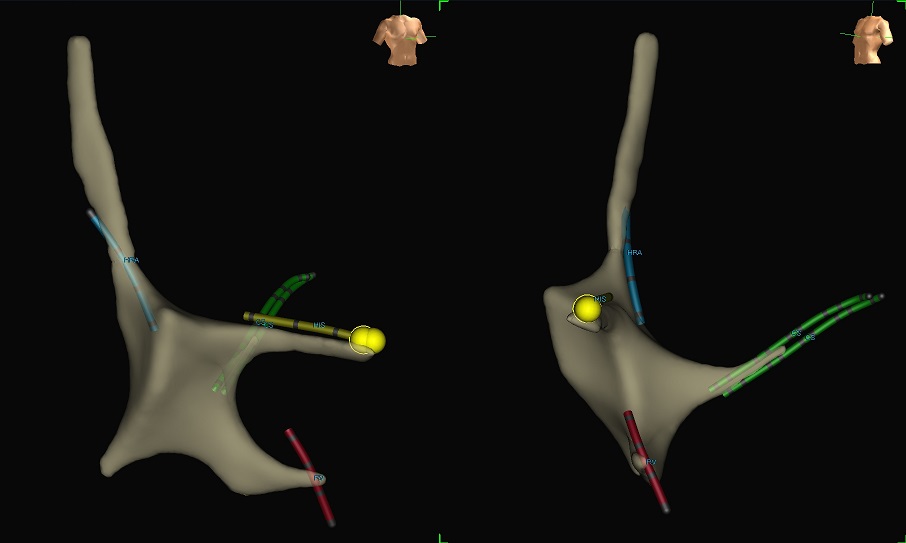

Με το νέο σύστημα ηλεκτροανατομικής χαρτογράφησης, ο Παιδοαρρυθμιολόγος Ανδριανός Κοντογεώργης, MBBCh, MRCP, PhD και η Διευθύντρια του Τμήματος Ηλεκτροφυσιολογίας, Αρρυθμιολόγος, Λίλιαν Μάντζιαρη, MD, MSc,PhD, τοποθέτησαν 4 ηλεκτρόδια μέσα στην καρδιά ενός παιδιού 10 ετών χωρίς καθόλου ακτινοβολία.

Το σύστημα απεικόνισε σε 3 διαστάσεις τη θέση των ηλεκτροδίων, αλλά και άλλα σημαντικά σημεία, όπως το δεμάτιο του His (κολποκοιλιακός κόμβος) για την ολοκληρωμένη διενέργεια της εξέτασης.

Η κλασική ηλεκτροφυσιολογική μελέτη η οποία διενεργείται σε Ηλεκτροφυσιολογικά Εργαστήρια τα οποία δεν διαθέτουν αντίστοιχο εξοπλισμό, γίνεται με τοποθέτηση ηλεκτροδίων (καλωδίων) σε κάποια συγκεκριμένα σημεία μέσα στην καρδιά τα οποία καταγράφουν την τοπική ηλεκτρική δραστηριότητα αλλά και μέσω των οποίων διεγείρεται ο καρδιακός μυς, χρησιμοποιώντας έναν εξωτερικό ηλεκτρονικό υπολογιστή. Για την τοποθέτηση των ηλεκτροδίων απαιτείται ακτινοσκόπηση (ακτινοβολία) προκειμένου ο ιατρός να προωθήσει και να τοποθετήσει στη σωστή θέση τα ηλεκτρόδια. Η νέα, σύγχρονη τεχνική που εφαρμόζεται στο Ιατρικό Διαβαλκανικό Θεσσαλονίκης, υπερέχει ως προς τη μη ακτινοβόληση του ασθενούς.